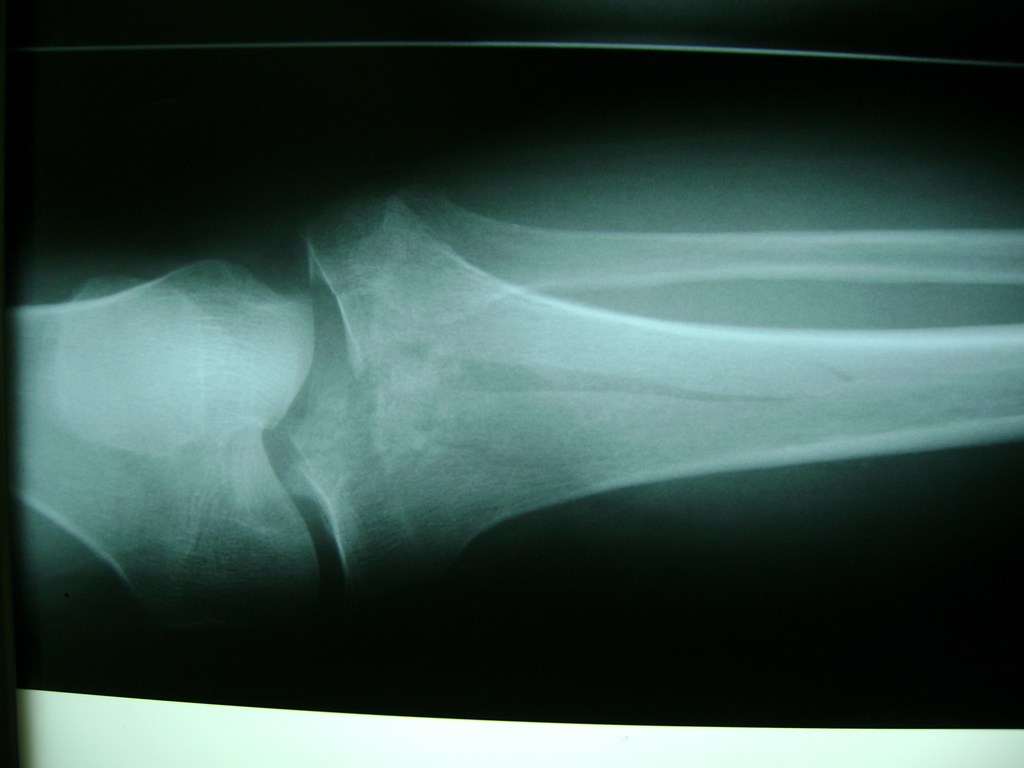

Cirugías de Húmero - Rodilla